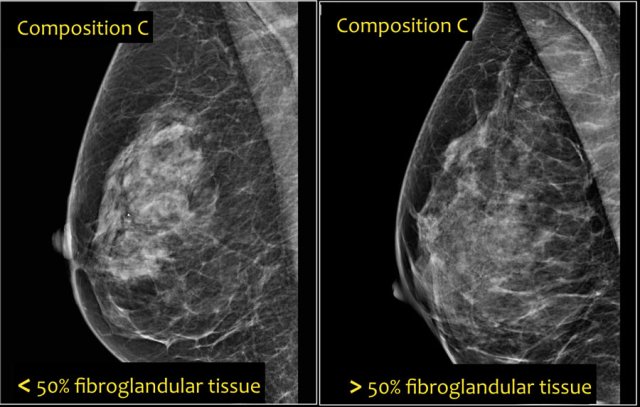

- c- The breasts are heterogeneously dense, which may obscure small masses.

Some areas in the breasts are sufficiently dense to obscure small masses.

Notice in the left example the composition is c - heterogeneously dense, although the volume of fibroglandular tissue is less than 50%.

The fibroglandular tissue in the upper part is sufficiently dense to obscure small masses.

So it is called c, because small masses can be obscured.

Historically this would have been called an ACR 2: 25-50% density.

The example on the right has more than 50% glandular tissue and is also called composition c.